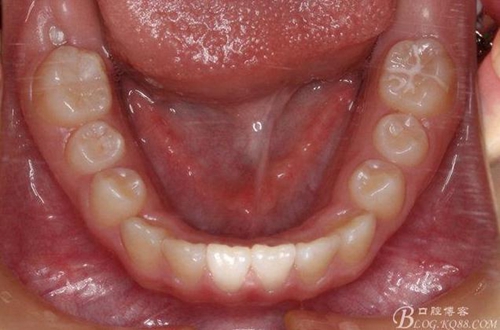

矯治第7個月復(fù)診:磨牙已有咬合接觸。上頜兩個6貼粘貼頰面管,矯治裝置成為真正的“2×4”矯治器。因?yàn)樯项M兩個3唇側(cè)錯位為完全弓外牙,所以在上頜弓絲上彎制了彎曲進(jìn)行避讓。兩個頰面管的近中設(shè)置了“阻擋曲”,目的是使上頜前牙進(jìn)一步唇移,同時為側(cè)方牙齒的萌出創(chuàng)造空間。停止使用固定式低位唇弓Activator。